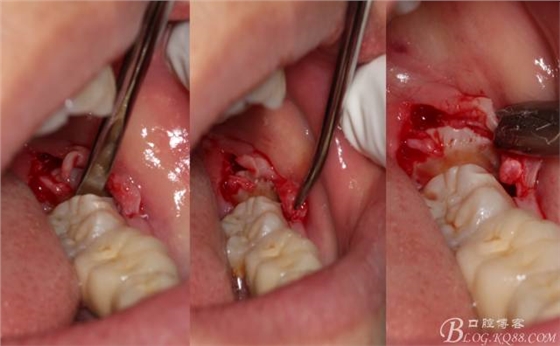

在取出阻力冠后,嘗試性看能取出全部的牙體不,就是取不出也能整體撬動牙根。

計劃總趕不上變化,何況是充滿變異的智齒。由于可操作空間較小,原來計劃橫向分根改成矢狀分根。